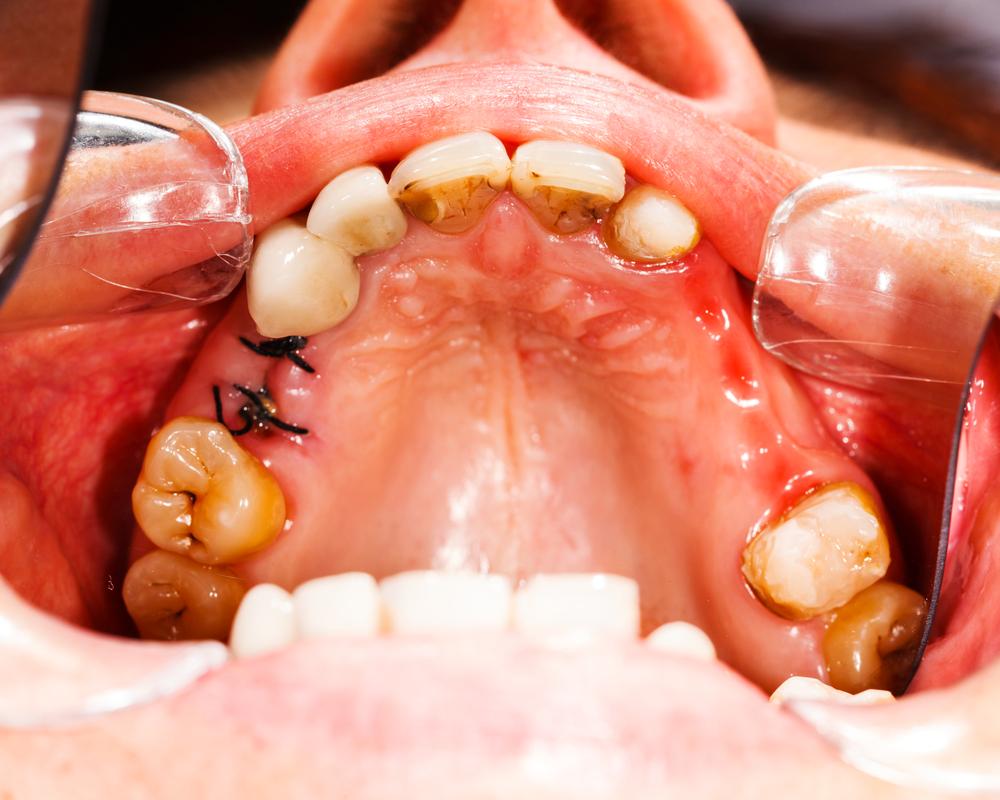

Caries, the other word for cavities, can be defined as the small holes or openings in the teeth that are a result of decaying tooth. To be able to know as to how to treat cavities, first, it’s important to know the causes of cavities. Cavities are a result of plaque and bacteria that builds its home on the teeth’s surface. Also, one who does not follow a good dental hygiene and does not have enough minerals in the diet is prone to having cavities in their teeth.

- Dark-stained pits and holes on the tooth/teeth.

- Breaking or chipping of the teeth, thus exposing a black inner surface.

There are some cavities, not visible to the naked eye that reside at the back of the mouth or between teeth. Now these cavities, although, don’t cause pain, can be identified only through ultrasound, x-rays, and/or fluorescent lighting. Therefore, it is extremely important to see your dentist regularly in order to keep your teeth in good health.